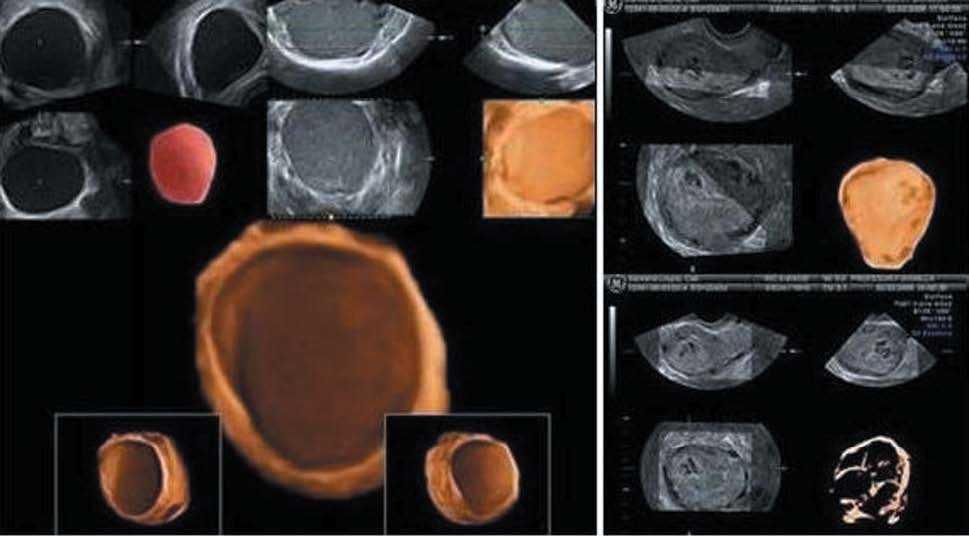

Patología mamaria

Tradicionalmente, el ultrasonido se ha utilizado como complemento de la mamografía para la detección de las alteraciones mamarias. Con el desarrollo de estas nuevas tecnologías se vislumbra un papel importante en el diagnóstico de las tumoraciones, sobre todo en el diagnóstico precoz, al incrementar notablemente la nitidez de la imagen obtenida (visión posible de microcalcificaciones) y aumentar la capacidad de análisis de la RDI por medio de las diversas modalidades de visualización, como las mostradas en la figura 11.

Figura 11.4D de mama. Otra excelente aplicación de esta nueva tecnología. A) Mastopatía fibroquística. B) Quiste con papilas y calcificaciones. C) Fibroadenoma. D) Prótesis mamaria mal colocada que hace ondas en su pared anterior. (Cedido gentilmente por L. Machado.)

Aunque hasta el momento los estudios realizados no muestran una diferencia significativa entre ultrasonografía 2D y 3D17,18, hay trabajos18 que señalan que la visualización del fenómeno de retracción en el plano de corte coronal en 3D tendría un significativo valor pronóstico para el cáncer de mama.